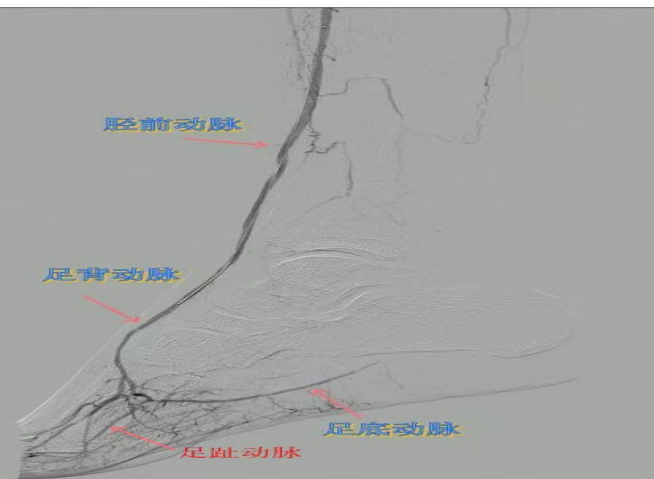

78歲男性患者,糖尿病合并高血壓、腦梗塞,右足持續(xù)疼痛伴冰涼發(fā)紺3個月。入院CTA顯示其右側(cè)股淺動脈全程閉塞,膝下三支動脈均閉塞。醫(yī)療團(tuán)隊(duì)在局部麻醉下,再次巧妙應(yīng)用“逆向開通技術(shù)”,經(jīng)脛后動脈——足底弓逆向開通足背動脈及脛前動脈。術(shù)后患者右足皮溫即刻回升,疼痛消失。術(shù)后結(jié)合中藥外治(換藥、熏洗、去腐生肌膏外敷)加速創(chuàng)面愈合,患者已順利出院。

影像檢查:CTA顯示右側(cè)股淺動脈全程閉塞,膝下三支動脈(脛前、脛后、腓動脈)完全閉塞。